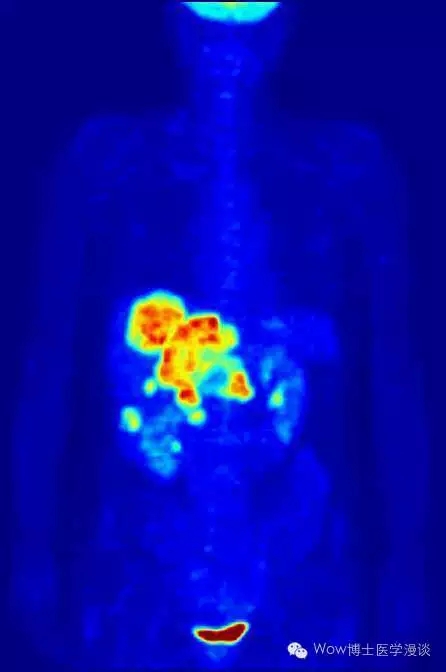

吕医生:简单来讲,PET/CT就是融合了PET和CT的影像学和核医学诊断技术。那么PET和CT又分别是什么呢?PET全称为:正电子发射型计算机断层显像,是核医学领域比较先进的临床检查影像技术,也是目前可在活体上显示生物分子代谢、受体及神经介质活动的新型影像技术。也就是说PET可以实时观察我们人体各个脏器和部位的生命代谢情况。

利用PET对人体进行全身扫描得到的图像

为什么PET有这么强大的功能呢?这要从它的工作原理说起。大家都知道我们的身体和器官的代谢是需要摄取能量的,这些能量可以由很多物质提供,比如葡萄糖。我们把葡萄糖标记上短寿命的放射性核素(如18F-FDG 、11C等),注入人体后,就可以通过PET观察身体各个器官或者部位吸收和利用葡萄糖的情况了。如果摄取的多,就说明这个部位的代谢旺盛,如果少,就说明代谢比较弱。

PET的这个特点使得它特别适合肿瘤的早期诊断。这是因为恶性肿瘤细胞往往生长特别快,所以需要特别多的能量供应因此就会摄取很多的葡萄糖。当这些葡萄糖标记了放射性核素后,在PET的图像中就会显示肿瘤部位为高代谢区域。通过这种方式可以实现对恶性肿瘤的诊断,诊断准确率在90%以上。而且恶性肿瘤是否发生了转移,以及转移的部位一目了然。还可以帮助医生判断肿瘤的进展和分期,判断患者是否需要手术以及手术切除的范围。